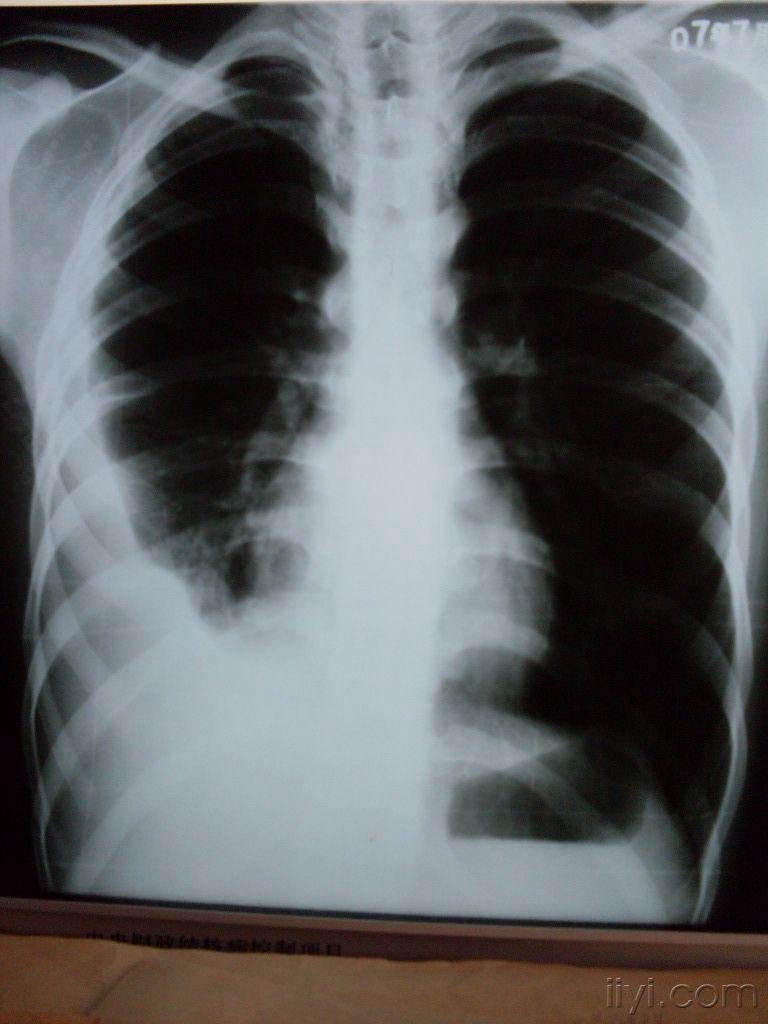

2 ,2,下图为包裹性胸腔积液:积液局限于某一部位,不随体位改变而改变